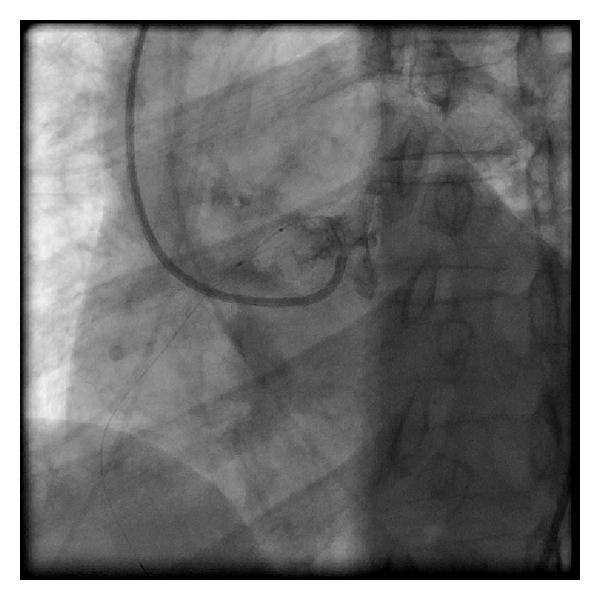

We then used a 6 F left coronary bypass guide catheter which could be aligned for wiring of the RCA (Figure 2). We used a 180 cm Hi-Torque floppy wire and an over-the-wire 2.5 × 15 mm Voyager balloon (both from Abbott Vascular, Santa Clara, CA, USA).

Our technique involves the use of a left bypass guiding catheter which is manipulated to align across from anomalous (RCA) (Figure 2) which allows for wire cannulation with a flexible wire and an over-the-wire balloon (Figure 3). We then pass the balloon into the distal RCA over the wire and exchange for a stiffer wire. If the stiffer wire allows for adequate support and visualization, we can complete the procedure with this guide. We have done this on two other patients. In this case, however, the support was tenuous and we used the XB guiding catheter which could be manipulated to engage the anomalous vessel (Figure 4). The procedure was then easily completed.